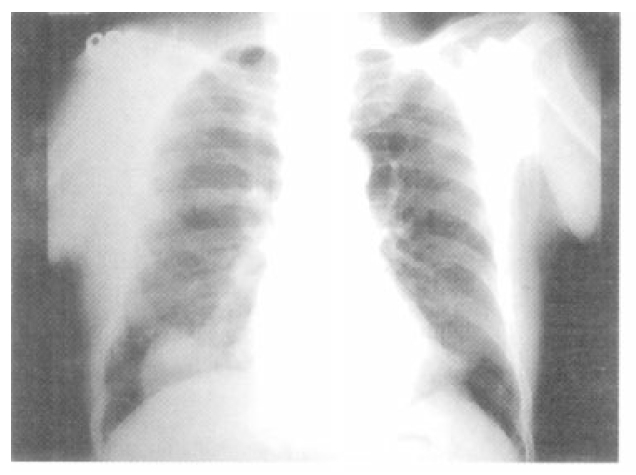

The laboratory tests were as follows: WBC count, 15.7×103/uL with 78% neutrophils, 13% lymphocytes, 7% monocytes, 1% eosinophils and others 1%; Erythrocyte sedimentation rate, 44 mm/h; hemoglobin, 14.4 g/dL; hematocrit, 41.4%; platelet count, 313×103/uL. Other laboratory findings including liver function, blood glucose level, renal function, electrolytes and urine microscopy, were all within normal limits. Arterial blood gas analysis on room air revealed a pH of 7.459, Pco2 of 36.8 mmHg and Po2 of 76.9 mmHg. The chest radiograph obtained at the time of admission showed a round mass in the right lower lobe (Figure 1). The chest CT scan performed at the referring hospital confirmed the presence of a 4×4 cm-sized, smoothly marginated, soft tissue density with central lower density in the right lower lobe.

Figure 1.

The chest PA shows a round mass with central low density in the right lower lobe.